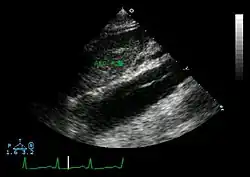

Ultrasound

The transesophageal echocardiogram (TEE) is a good test in the diagnosis of aortic dissection, with a sensitivity up to 98% and a specificity up to 97%. It has become the preferred imaging modality for suspected aortic dissection. It is a relatively noninvasive test, requiring the individual to swallow the echocardiography probe. It is especially good in the evaluation of AI in the setting of ascending aortic dissection and to determine whether the ostia (origins) of the coronary arteries are involved. While many institutions give sedation during transesophageal echocardiography for added patient comfort, it can be performed in cooperative individuals without the use of sedation. Disadvantages of TEE include the inability to visualize the distal ascending aorta (the beginning of the aortic arch), and the descending abdominal aorta that lies below the stomach. A TEE may be technically difficult to perform in individuals with esophageal strictures or varices.

-

Aortic dissection with an intramural hematoma as seen on TEE